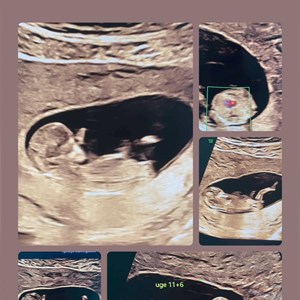

22. juni 2024

Tidlig scanning på foster uge 11+6 Når mor og far ser 1. gang hvor meget baby kan OG kan...